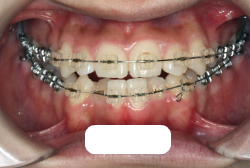

歯科矯正用アンカースクリューを用いた症例(骨格性反対咬合 非抜歯治療)

「ものがうまく噛めない」という主訴で来院したケースです。診断の結果、「骨格性反対咬合に伴う咬合不良+軽度叢生」と判明しました。原因としては特に下顎の左側が過成長したため、骨格性反対咬合になり、特に左側での噛み合わせが非常に悪くなっていると診断しました。初診時の写真を見ると、上下の正中線の大きなズレ、左側の噛み合わせの不良がはっきり分かります(黄色の矢印と緑の矢印は一致しているのが正しい状態です)。

そもそも、このような状態となっているのは骨の大きさに問題があるため生じていますので、場合によっては、「外科矯正」によって下顎の骨を外科的に縮めることで修正します。患者様が外科矯正をご希望されない場合は、従来ですと上下左右の小臼歯抜歯を行い矯正するのが普通です。

今回の患者様の場合は、「外科」も「小臼歯抜歯」も拒否されましたので、歯科矯正用アンカースクリュー(以下 アンカースクリュー)を用いて、下顎の歯列全体を後方に下げるという方法を取りました。

治療中の写真で、アンカースクリューより歯を後ろへ牽引しているのがお分かりいただけるかと思います。牽引を1年ほど続け、途中補助的に上下にゴムをかける(これを顎間ゴムと言います)手法なども追加し、全体で21ヶ月で治療を終えることが出来ました。

結局歯の本数を減らすことなく、すべてご自分の歯を残して、正しい配列と噛み合わせにすることができました。凸凹があまりひどくないため、簡単そうに見えると思いますが、このケースの初診の状態を見ると、熟練の矯正歯科医でも悩みのつきないケースです。まして、外科も出来ない、抜歯もイヤ、と言うことになると、従来の方法では治療不可能と考えられるのですが、アンカースクリューを使うことで最近は不可能が可能となってきました。